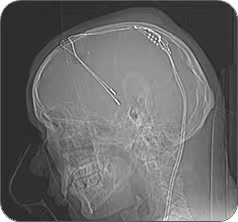

张文川介绍,脑深部电刺激(DBS)俗称“脑起搏”,这是一种通过电刺激脑深部特定神经核团,治疗帕金森病、癫痫、震颤及肌张力障碍等多种疾病的神经调控技术。

脑深部电刺激治疗手术示意图,患者的脑内植入电极,然后通过延长线连接刺激器。网络图

手术过程中,在张文川的指导下,医生廖陈龙为患者实施了双侧苍白球内侧脑深部电刺激治疗手术。术中,通过微电极记录系统描记不同深度脑深部神经核团的电信号,结合术前多模态影像融合技术,精准定位靶点。同时,通过术中患者的反馈和体征评估,即时确认了手术疗效。